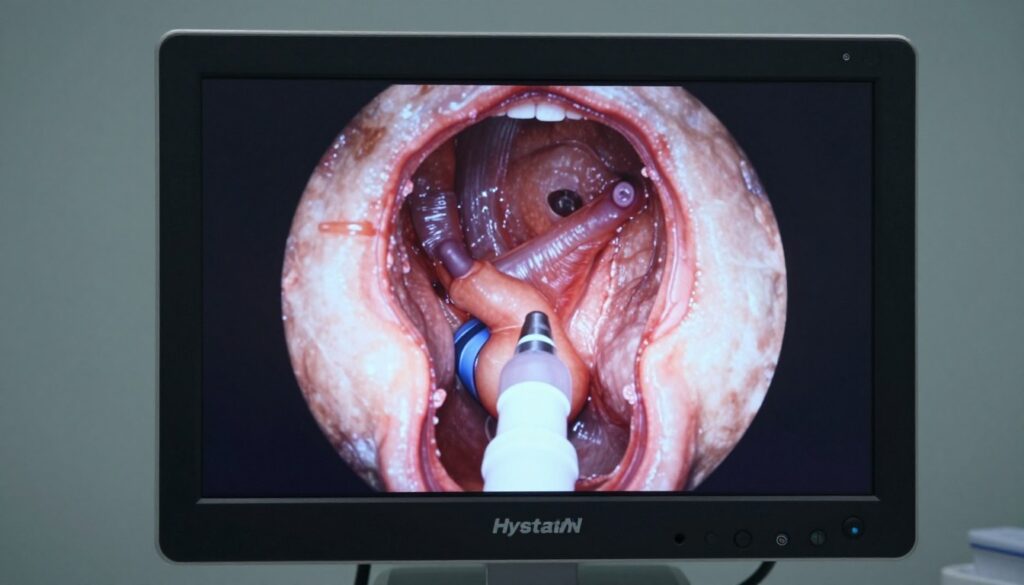

Hysteroscopy allows direct visualization of the uterine cavity. A thin telescope passes through the cervix. Doctors can diagnose and sometimes treat abnormalities during the same procedure. Small polyps or fibroids can be removed. Uterine septum or scar tissue can be corrected. Hysteroscopy requires anesthesia and occurs in a surgical setting.

Multiple surgical approaches exist for myomectomy. Hysteroscopic myomectomy removes submucosal fibroids through the cervix. Laparoscopic or robotic myomectomy uses small abdominal incisions. Abdominal myomectomy requires a larger incision. Surgery carries some risks. Fibroids may recur. In severe cases, hysterectomy becomes necessary. Uterine artery embolization shrinks fibroids but may impact fertility.